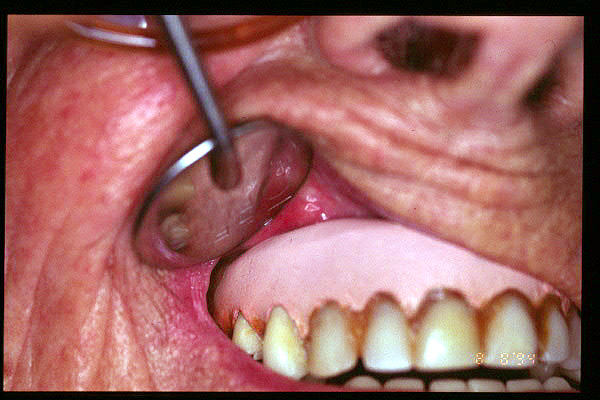

CM Hiperplasia por prótesis